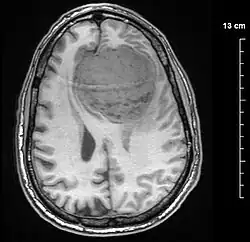

Meningiomas are visualized readily with contrast CT, MRI with gadolinium,[23] and arteriography, all attributed to the fact that meningiomas are extra-axial and vascularized. CSF protein levels are usually found to be elevated when lumbar puncture is used to obtain spinal fluid. On T1-weighted contrast-enhanced MRI, they may show a typical dural tail sign absent in some rare forms of meningiomas.[18]